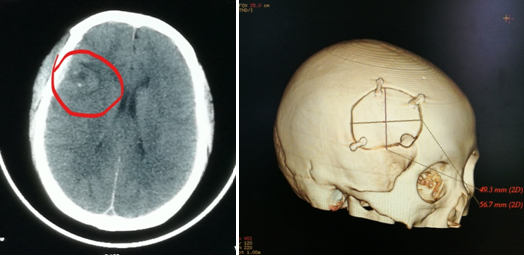

近日,我院收治一病友,因头痛检查发现右额叶运动区旁一大小约1cm病变,考虑海绵状血管瘤。

组图:头颅MRICT发现中央前回前脑实质内占位病变,考虑海绵状血管瘤

完善准备后,通过三维立体定位,找到了病变位置及其与脑沟的关系。术中发现,因患者在患病过程中病变部位曾反复出血,胶质增生及黄染,脑沟深处可见明显病灶区域(定位分毫不差)。术中显微镜下分离脑沟及血管,周围组织无损伤,精准切除病变。病人无任何功能缺失,康复出院。